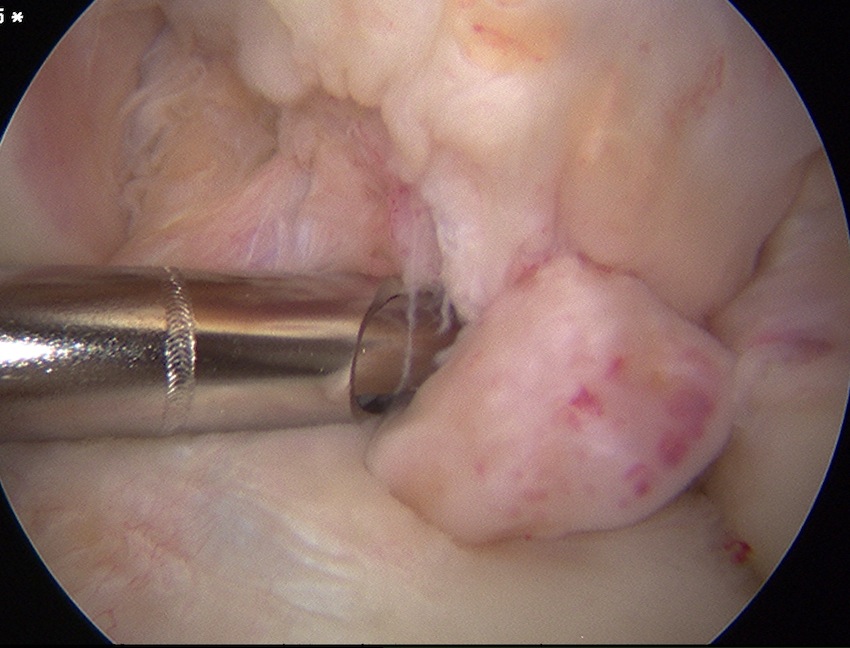

ICRS Arthroscopic Classification

1. Cartilage Intact

2. Partial discontinuity but stable on probing

3. Completely detached but insitu

4. Fully detached with crater & loose body

A. Chondral Fragment Salvageable

- recent

B. Chondral fragment unsalvageable

- increased in size / change in shape